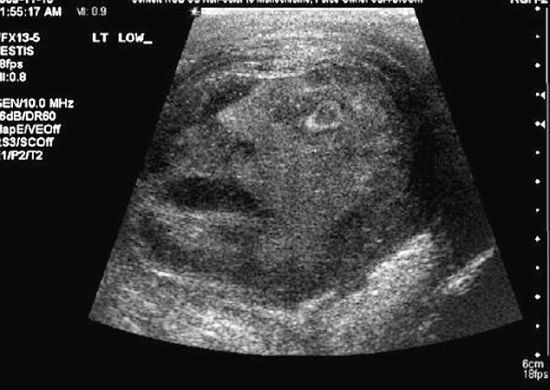

一幅超声波图像,人脸图案清晰可见。这张脸表情痛苦,右侧的眼睛睁大,嘴巴张开

新浪科技讯 北京时间11月5日消息,据国外媒体报道,从火星上的山脉到薄烤饼,我们都曾看到人脸图案。这一次,加拿大安大略省的两位科学家又在睾丸肿瘤中拍到令他们吃惊的人脸,脸上表情痛苦,嘴巴张开。据悉,这个可怕的人脸图案是在对一名45岁的睾丸肿瘤患者进行超声波检查时拍到的。

拍到睾丸肿瘤人脸后,安大略省皇后大学的格雷格-罗伯茨博士和纳吉-杜玛博士将这幅令人吃惊的图像递交《泌尿学》杂志。9月,《泌尿学》杂志接受了这幅图像,作为一个特殊病例的图片说明,取名为“睾丸疼痛之脸”。罗伯茨和杜玛表示:“在图像中看到这个男性面部图案,医生和其他工作人员都感到非常吃惊。这幅图像是在进行超声波检查时拍摄的。脸上的表情很痛苦,嘴巴张开,似乎得了睾丸附睾炎。”